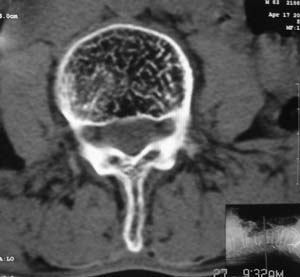

以下是引用余辉在2008-4-27 17:12:00的发言:[br]骨质疏松伴病理性压缩性骨折,椎骨骨松质密度减低,椎体骨小梁稀疏且普遍呈火柴头样改变,椎体无膨胀,无软组织肿块

以下是引用mzh123在2008-4-27 19:33:00的发言:[br]除压缩骨折表现外 还有许莫氏结节改变

以下是引用随光逐影在2008-4-27 21:29:00的发言:[br]除压缩性骨折外,还有许莫氏结节及骨质疏松表现。